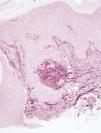

HistopatologíaSe practicó una biopsia cutánea de uno de los bordes de las placas donde se observaba acantosis de la epidermis con hiperqueratosis, sin presencia de neutrófilos intraepidérmicos y en la dermis, un material basófilo, que se eliminaba a través de la epidermis (fig. 2). Mediante la tinción histoquímica con orceína comprobamos que se trataba de fibras elásticas (fig. 3).

En el estudio histológico de las lesiones se observa hiperqueratosis con o sin paraqueratosis, y la característica eliminación de material a través de la epidermis, que la tinción con orceína permite identificar como fibras elásticas.